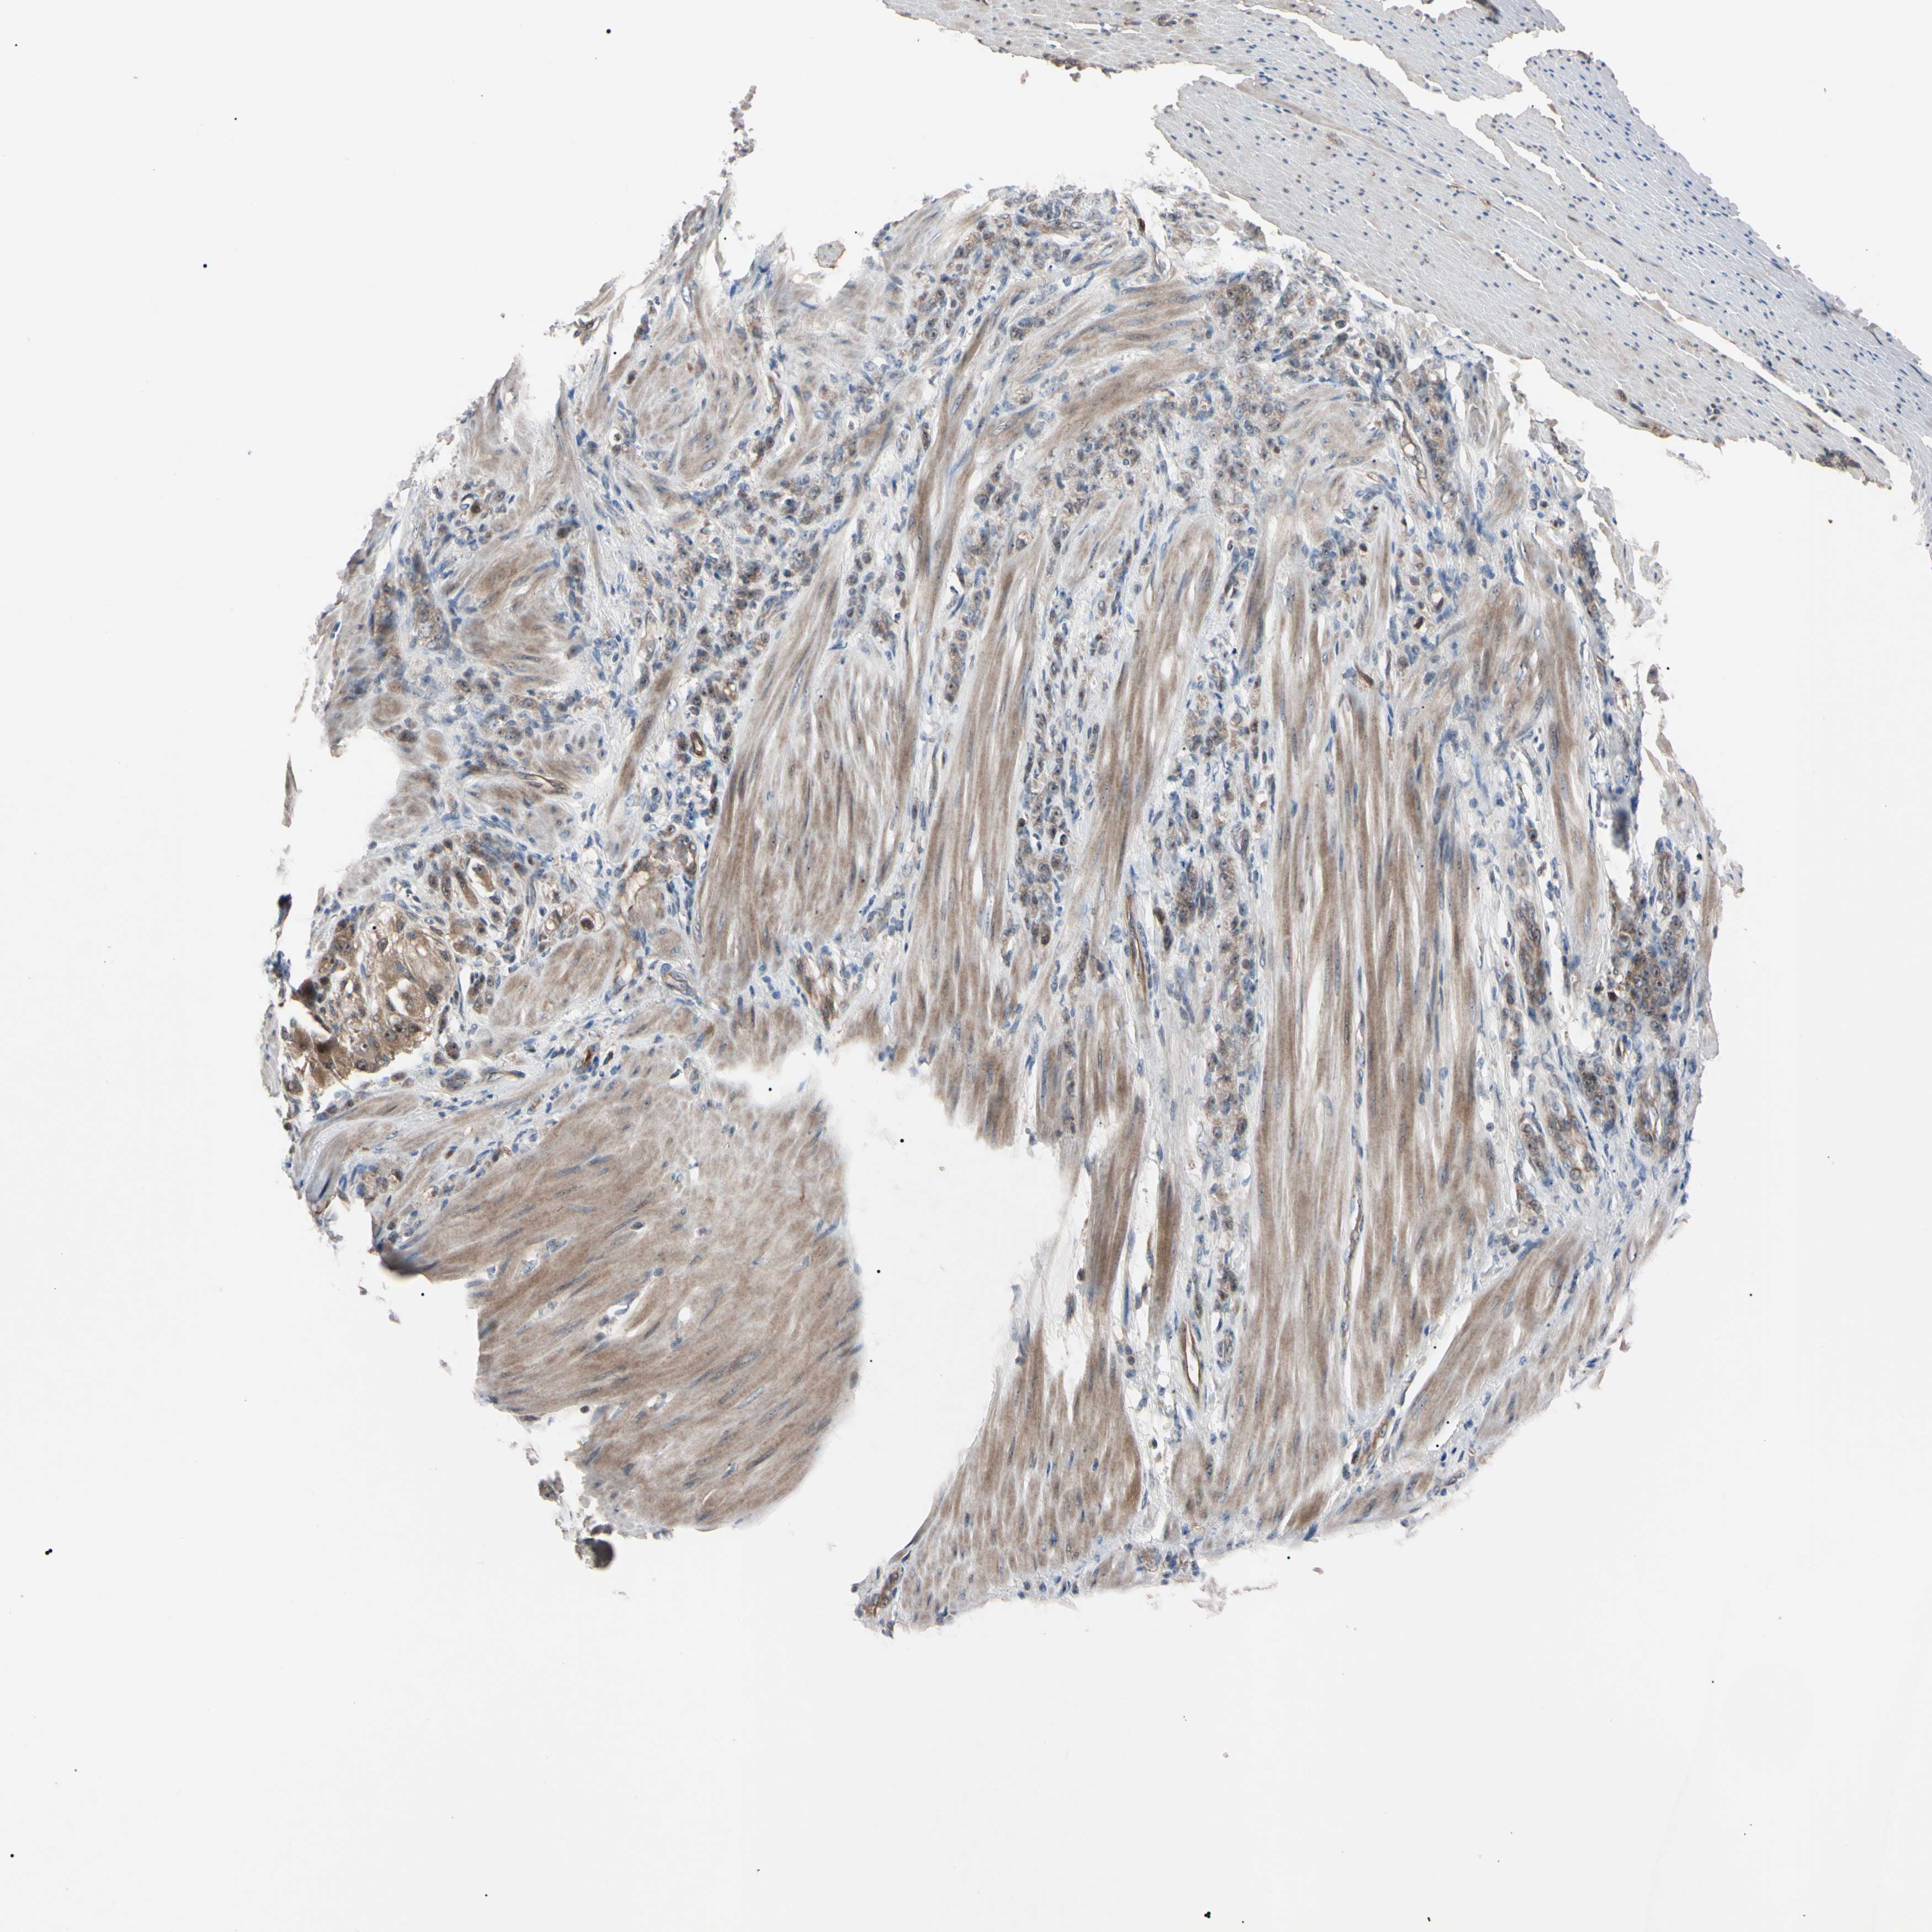

STOMACH CANCER - Protein expressioni

A mouse-over function shows sample information and annotation data. Click on an image to view it in a full screen mode. Samples can be filtered based on level of antibody staining by selecting one or several of the following categories: high, medium, low and not detected. The assay and annotation is described here.

Note that samples used for immunohistochemistry by the Human Protein Atlas do not correspond to samples in the TCGA dataset.

Antibody stainingi

Antibody staining in the annotated cell types in the current human tissue is reported as not detected, low, medium, or high, based on conventional immunohistochemistry profiling in selected tissues. This score is based on the combination of the staining intensity and fraction of stained cells.

Each image is clickable and will lead to virtual microscopy that enables deeper exploration of all samples and also displays staining intensity scores, fraction scores and subcellular localization as well as patient and tissue information for each sample.

Antibody HPA008052

Antibody CAB010277

Staining

High

Medium

Low

Not detected

Intensity

Strong

Moderate

Weak

Negative

Quantity

>75%

75%-25%

<25%

None

Location

Nuclear

Cytoplasmic/membranous

Cytoplasmic/membranous,nuclear

Adenocarcinoma, NOS

Adenocarcinoma, High grade